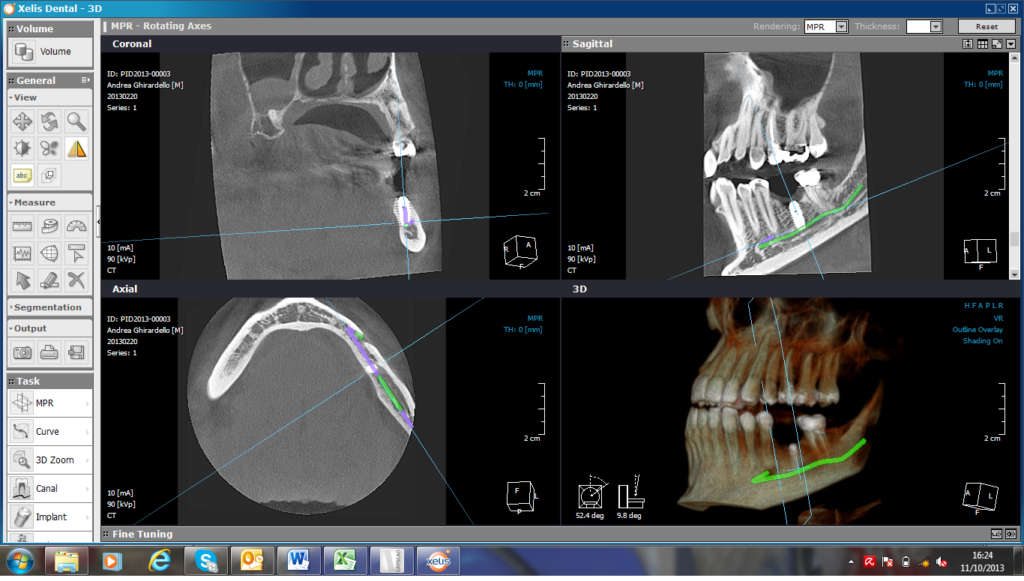

TAC CONE BEAM

La C.T. Cone Beam (CTCB) è il nuovissimo sistema di TAC dentale aperta, che ha rivoluzionato il mondo della radiologia digitale, è a basso dosaggio ed è utilizzata per la diagnosi delle patologie dell’apparato masticatorio, del distretto maxillo-mandibolare e nell’ambito otorinolaringoiatrico.

La C.T. Cone Beam, ha sostituito l’utilizzo della TAC tradizionale in Odontoiatria, poiché evidenzia le immagini con migliore definizione, e con una dose radiogena 20 volte inferiore, il tutto rigorosamente con la metodica di ricostruzione 3D.

L’esame dura in media, 13 secondi, il paziente non viene più posizionato all’interno di un’apparecchiatura a forma di tunnel, ma esegue l’esame in piedi, così potrà fare in studio, in pochi minuti, un esame che avrebbe potuto eseguire solo nei centri radiologici specializzati.

Per  questo vi è la possibilità per il Dottore e di avere in poco tempo un’esame 3D preciso e dettagliato, la risoluzione delle immagini è sub millimetrica e pertanto si possono fare valutazioni anatomiche estremamente precise, condizione essenziale per una diagnosi accurata ed efficace.

Un’altra caratteristica dell’esame è la possibilità di ottenere con un’unica scansione la ricostruzione di entrambe le arcate mascellari, superiore ed inferiore, senza costi ed esami aggiuntivi.

Oltre a ciò, tramite l’esame Cone Beam si possono visualizzare le strutture nervose (nervo alveolare inferiore), le vie aeree ed i seni paranasali.

Oggi l’esame T.C. Cone Beam rappresenta quindi il golden standard, degli esami radiologici in odontoiatria essendo un esame completo, dal costo contenuto, rapido nell’esecuzione e più rispettoso della biologia.